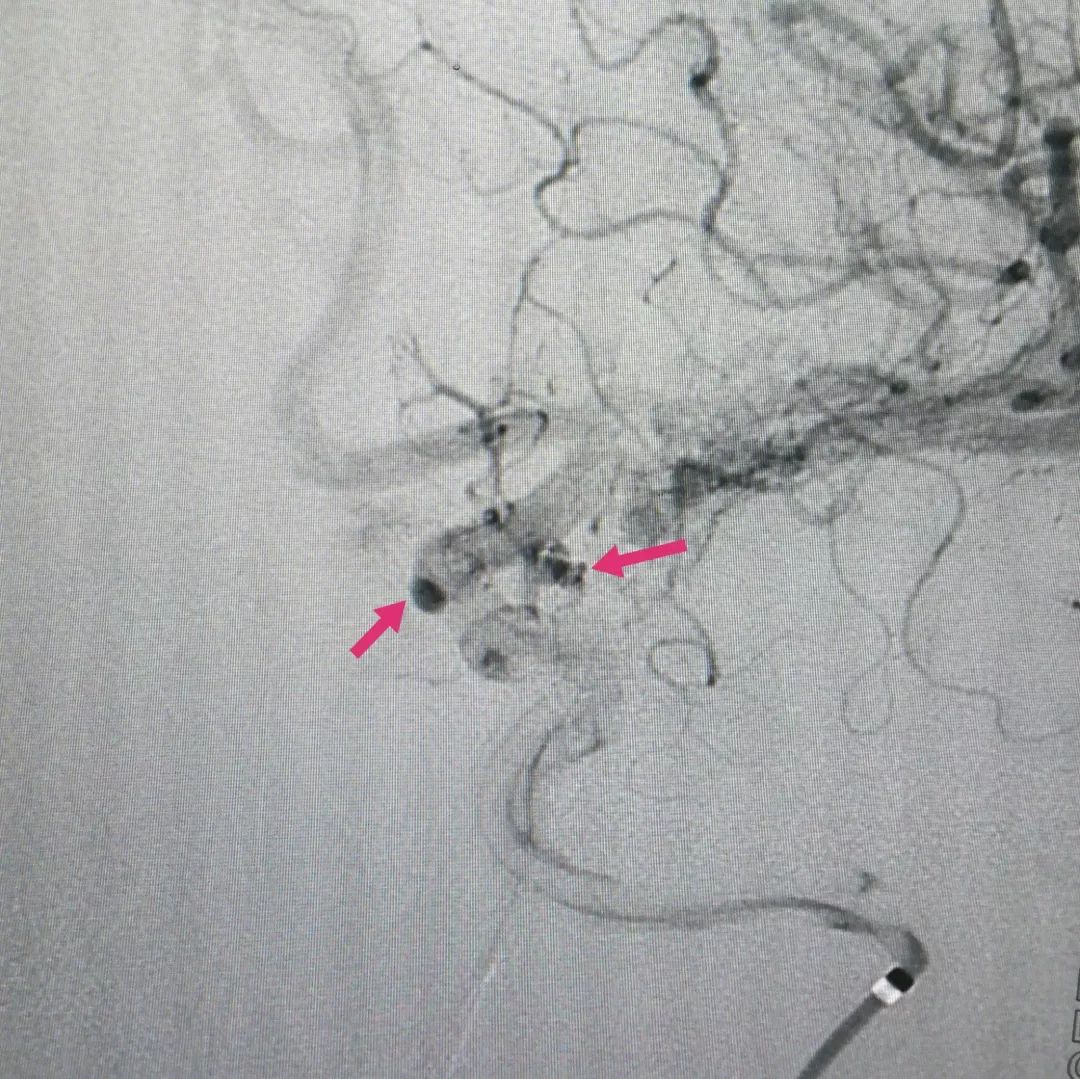

手术后复查脑血管造影可见动脉瘤已经大部分再显影,残余瘤腔内造影剂明显停留(下图),提示动脉瘤内血流缓慢,而这就是密网支架的独特效果。根据冬雷脑科医生集团的临床经验,微小动脉瘤一般半年后的完全治愈率是100%